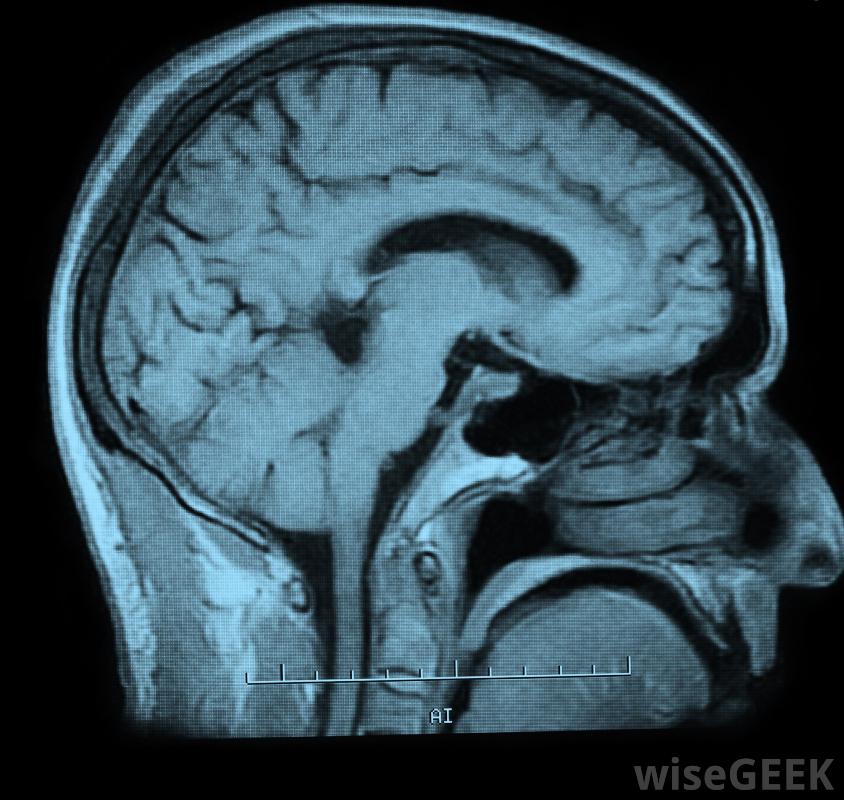

三級護理是指當有人遇到不明原因的問題時所接受的醫療服務。病人有不能立即確定病因的癥狀時,可以轉診給二級護理專家。然而,三級護理服務通常涉及心臟或其他器官、腦的專門治療或手術手術、燒傷護理和癌癥治療通常也屬于這一類。接受腎臟透析、接受磁共振成像(MRI)或計算機斷層掃描(CT)的患者,或適合于面部或身體其他部位的假肢經常尋求三級護理服務。

三級護理提供者通常可以獲得最詳細的醫學影像工具以及其他資源。

咨詢式醫療保健通常在二級提供,然后可以轉診到專門針對其病情的三級護理服務機構,或者從一個機構轉到三級轉診醫院。例如,這類醫院可以專門從事心臟病或癌癥的治療,這些設施的服務包括高分辨率、無創性的醫學掃描,除了心臟手術,如導管插入術。

接受MRI或CT掃描的患者通常會尋求三級護理服務。